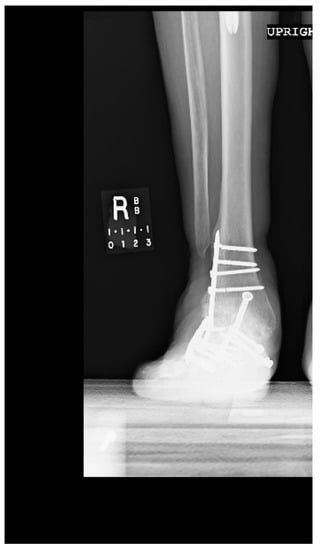

1.1.4. Post-Operative Imaging